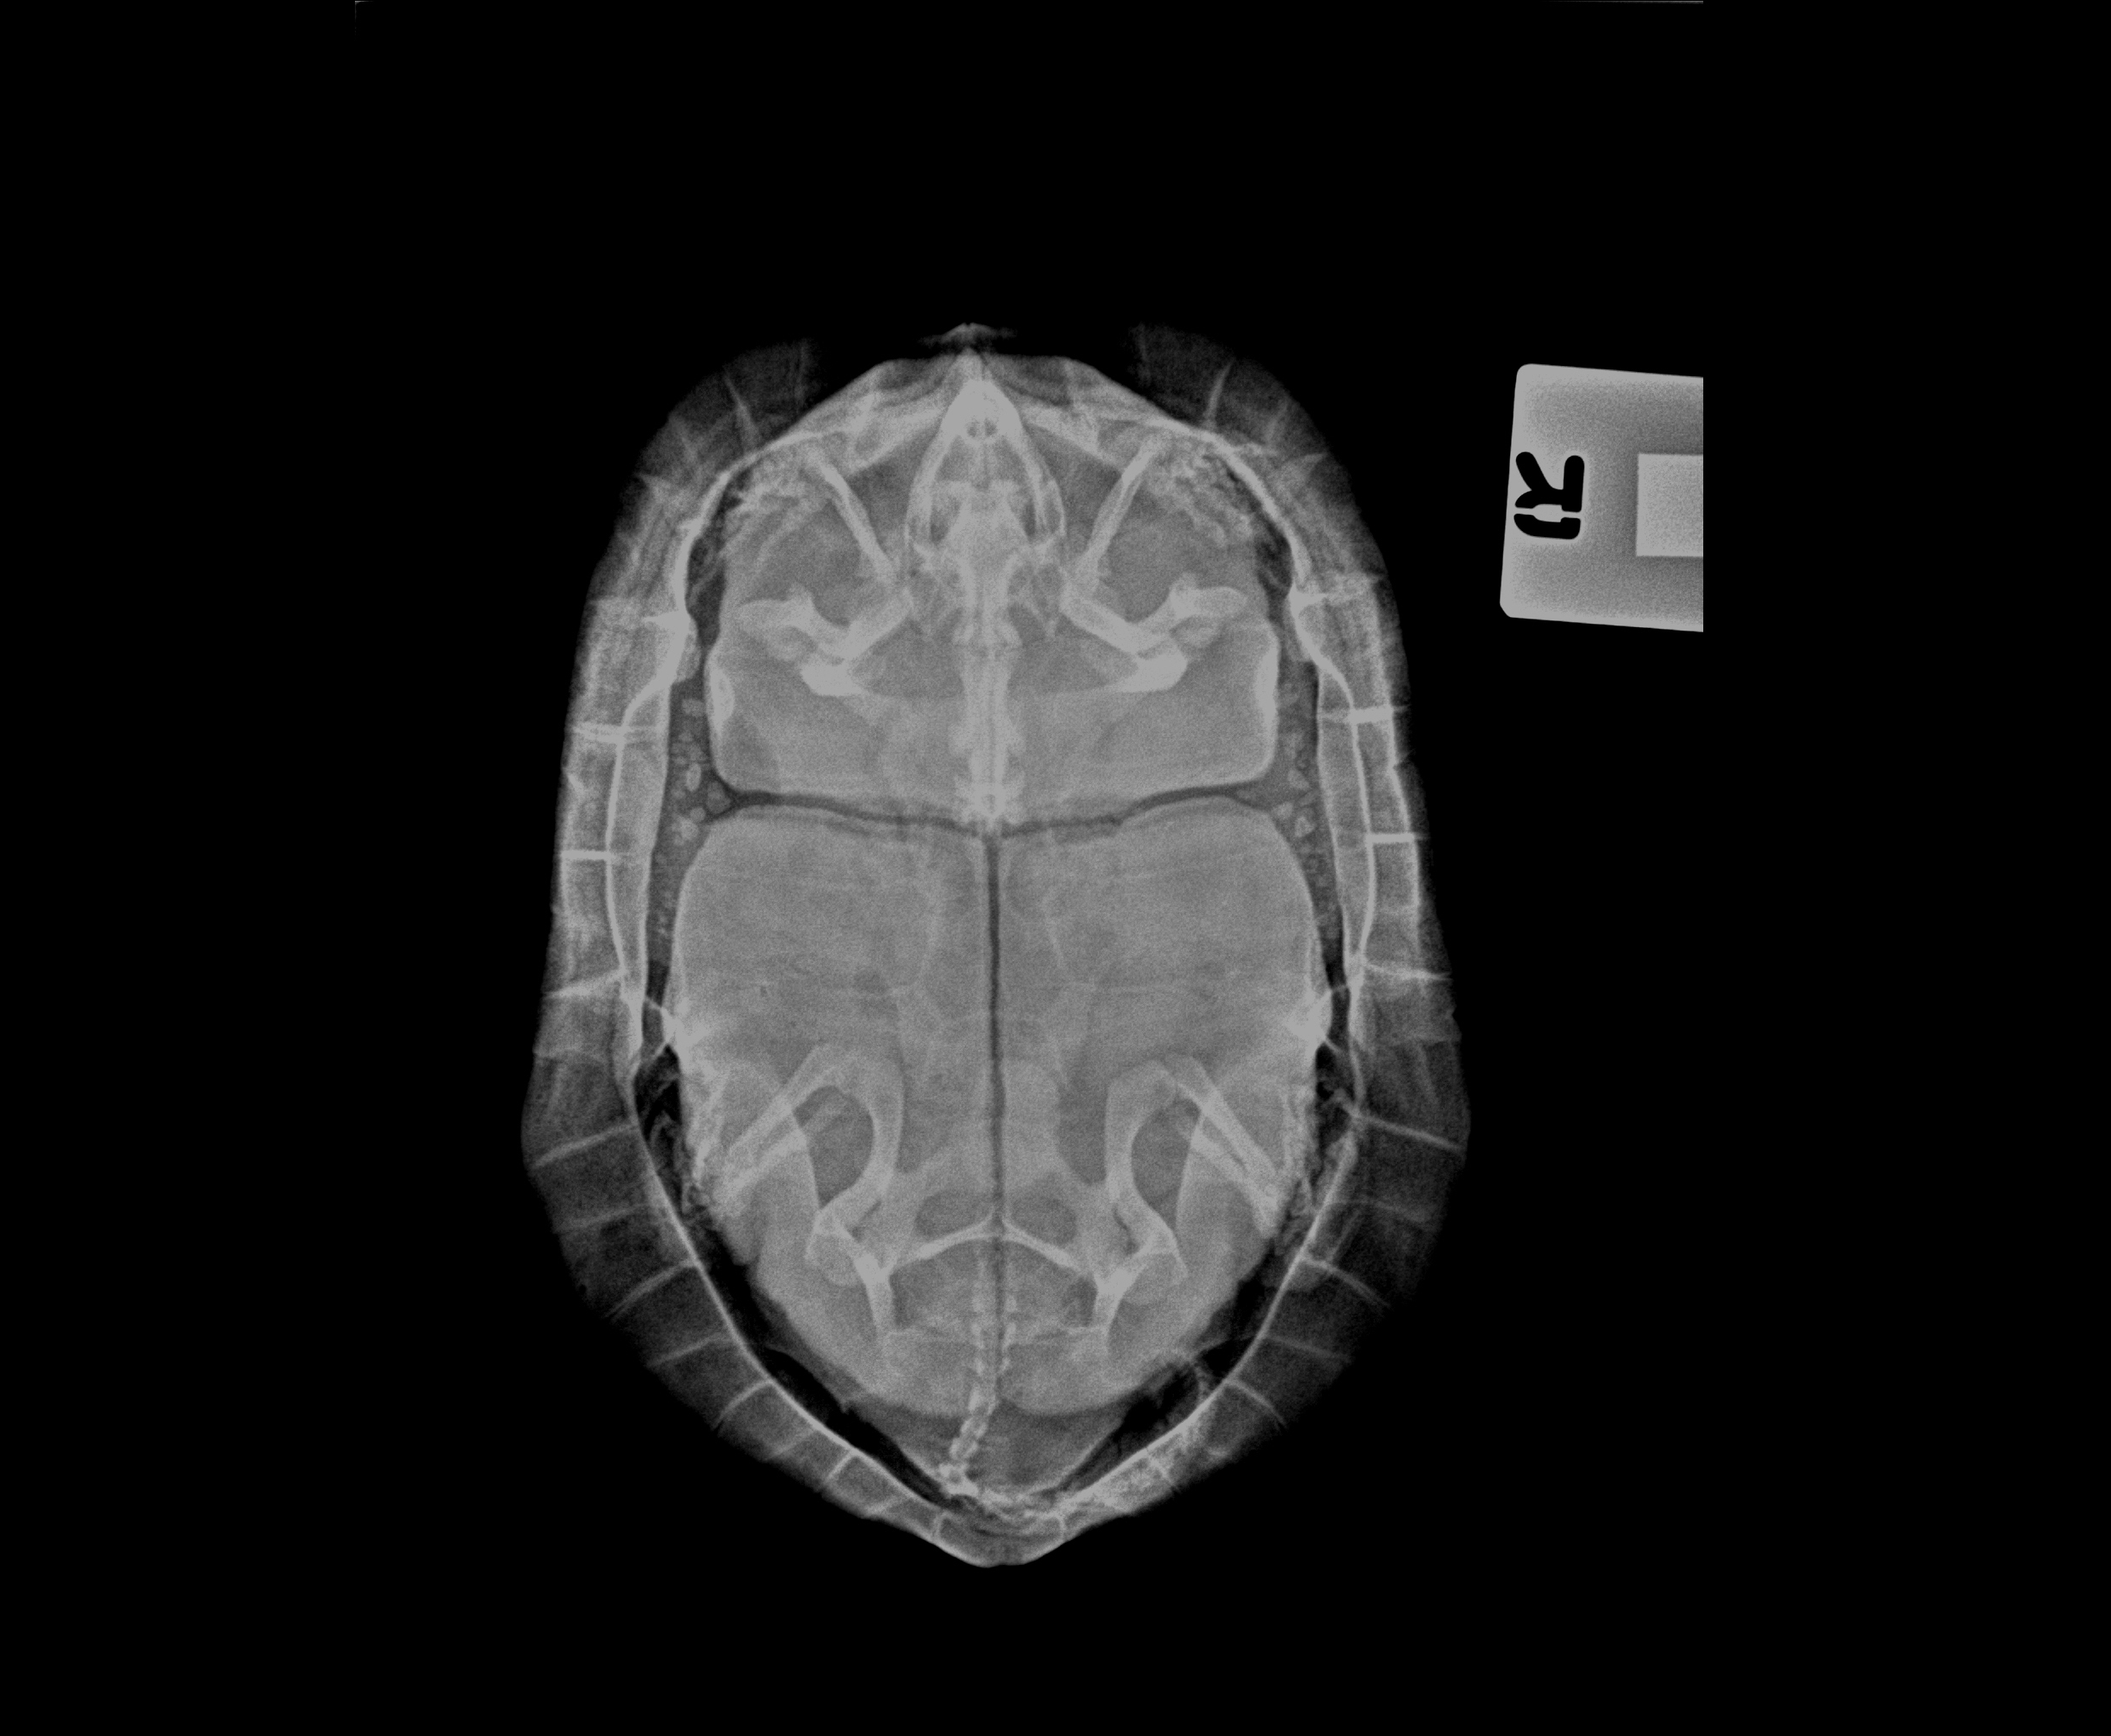

There was a high density oval object inside the caudal region of the coelomic cavity. It could be obstructed in the intestines, urinary bladder or reproductive tracts resulting in loss of appetite.

Siu Bo bear the risk of surgical option if failed to respond the course of medication.

Fortunately, after the intensive care and medical therapy, this oval object was able to pass out. It was a calcified urinary bladder stone. Siu Bo continued the second course of medication and recovered gradually. Siu Bo is now active and eating well again. It’s so blessing.